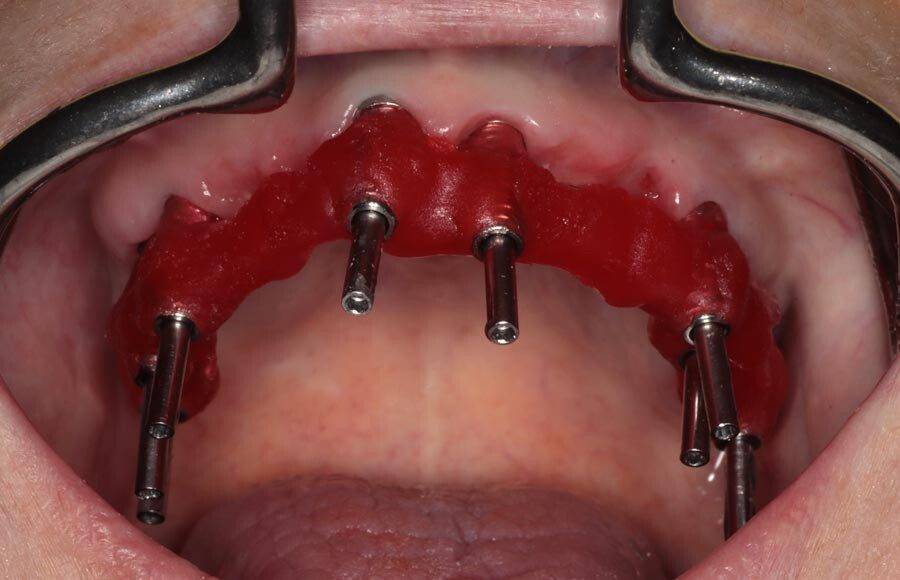

Splinted impressions are made for maximum accuracy at this stage. Records are completed and sent to our partner lab so they can start creating wax prototypes for us to test.